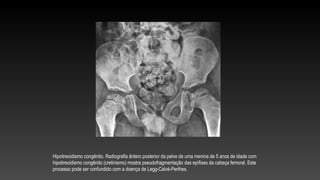

Hipotireoidismo congênito. Radiografia ântero posterior da pelve de uma menina de 5 anos de idade com

hipotireoidismo congênito (cretinismo) mostra pseudofragmentação das epífises da cabeça femoral. Este

processo pode ser confundido com a doença de Legg-Calvé-Perthes.